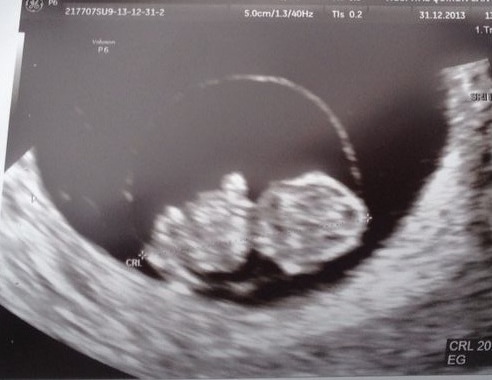

Pero bueno, para no terminar de una forma tan seria, y como homenaje a las madres y a la valentía de las que están a punto de serlo, esta foto.ecoEsta foto que es el resultado de dos personas que han decidido tener un hijo y que en las dos, os aseguro, está ese mismo “gen” de la generosidad, y el de la ilusión compartida.